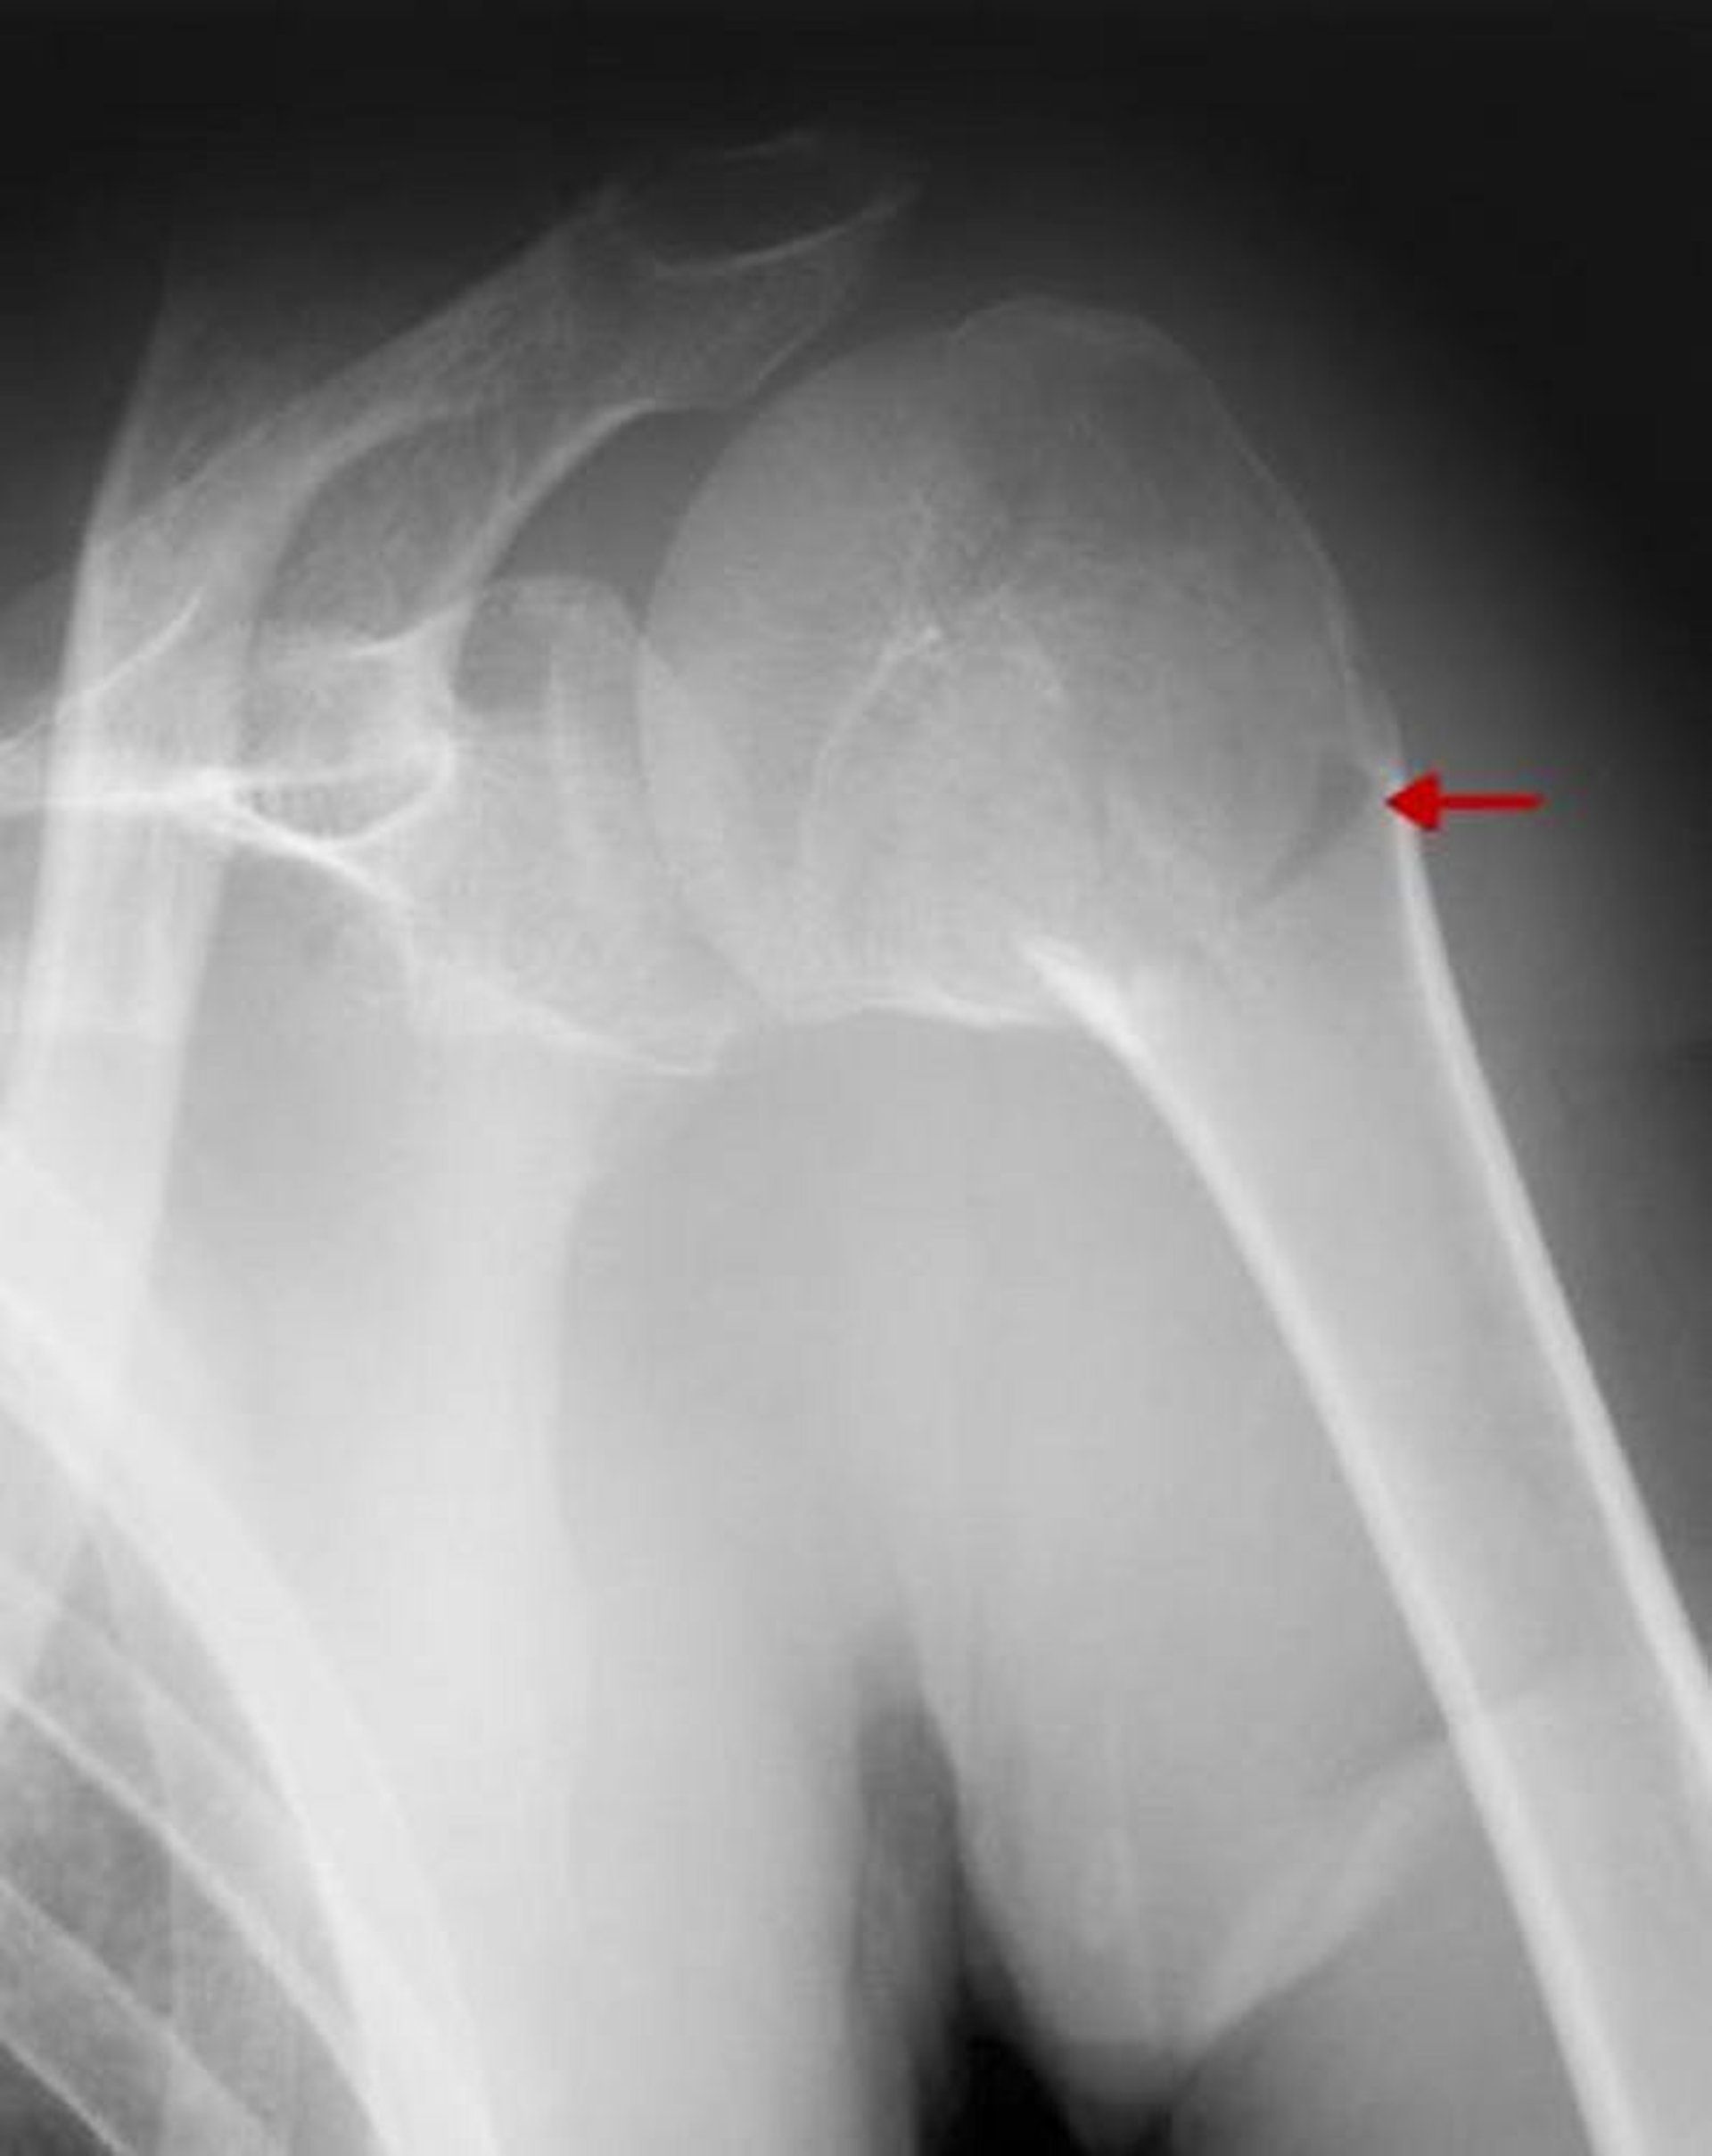

Fratura proximal do úmero

Essa fratura envolve o colo cirúrgico. Como não há nenhum desvio significativo com angulação > 45°, é uma fratura de uma parte.